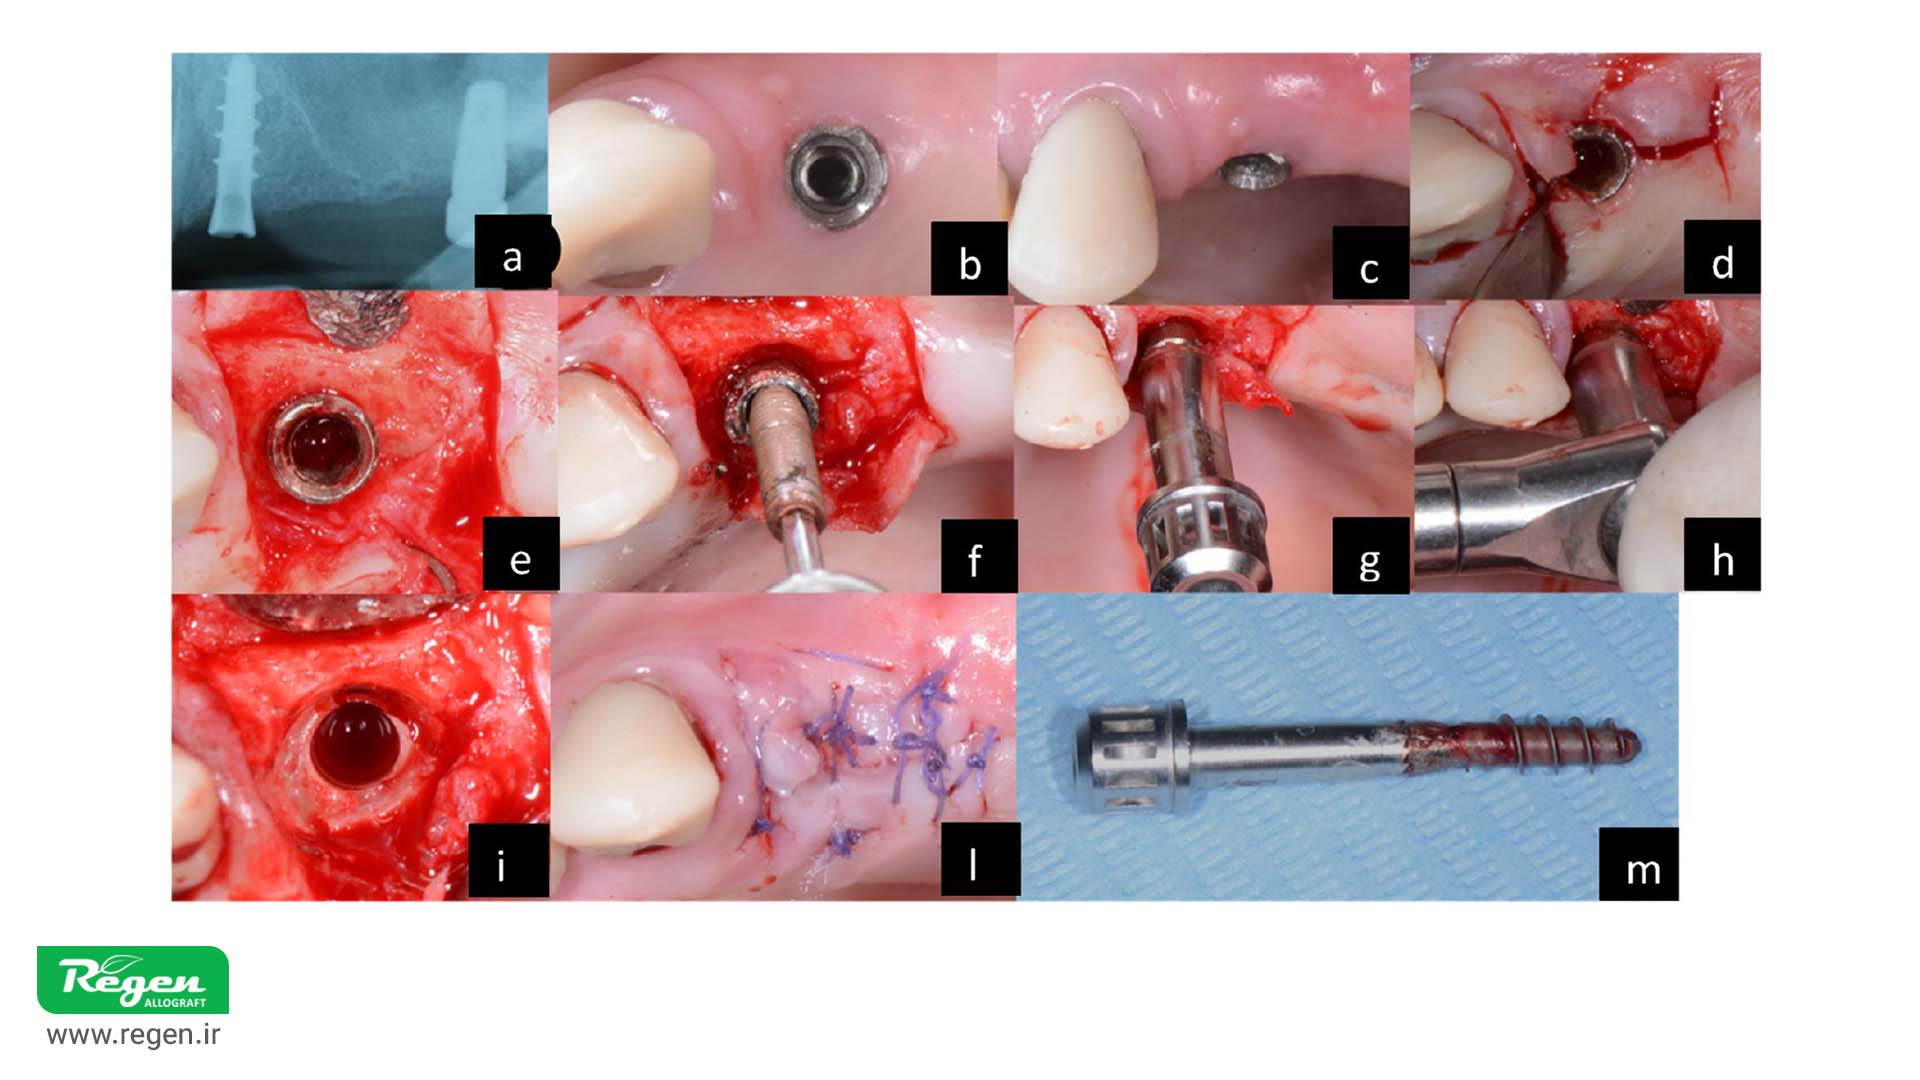

Counter-Torque Ratchet Technique (CTRT) for Dental Implant Removal

The success of implant removal using the Counter-Torque Ratchet Technique (CTRT) depends on several critical factors, including the type of implant-abutment connection, the implant’s shape and geometry, and the degree of osseointegration surrounding the implant. This method is considered one of the most effective and conservative techniques for explantation. However, certain conditions must be met for safe and successful use:

- The implant-abutment connection must be intact.

- Narrow implants may be at higher risk of fracture.

If the connection is compromised or unsuitable, CTRT is not recommended.

The components of a CTRT kit typically include a connection screw, a specialized driver for turning, and a torque wrench that enables precise measurement of the torque required for implant removal. These kits are usually universal and compatible with most implant systems. Examples of such kits include the Straumann® Counter-Torque Kit, Neo Fixture Remover Kit, and BTI Implant Extraction .System